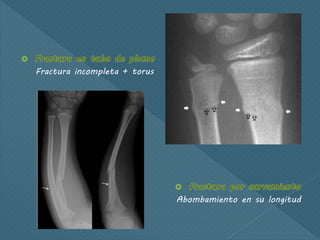

Fractura incompleta + torus

Abombamiento en su longitud

Fractura incompleta +torus Abombamiento en su longitud